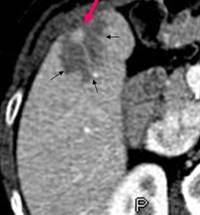

Une stéatose focalisée périlésionnelle est classiquement retrouvée dans les métastases hépatiques des insulinomes malins (1-4). Cette stéatose pourrait être secondaire à l’élévation de l’insulinémie qui, lorsqu’elle est prolongée, inhibe l’oxydation des acides gras libres et stimule leur estérification en triglycérides. Ces derniers s’accumulent alors dans les hépatocytes et génèrent ainsi une stéatose. Plus rarement a été décrite la possibilité d’une stéatose pancréatique périlésionnelle dans les insulinomes (2, 5). Le mécanisme physiopathologique de cette stéatose pancréatique est probablement le même qu’au niveau hépatique. La possibilité d’une ischémie péritumorale potentiellement responsable de modifications de la composition en graisse du tissu sain péritumoral ne peut cependant être exclue (5). Des lésions de stéatose péri lésionnelle ont également été décrites dans des glucagonomes (4). Une élévation prolongée du glucagon pourrait être responsable d’une augmentation de la lipolyse dans les hépatocytes avec apparition d’une stéatose périlésionnelle.  En conclusion, la mise en évidence d’une stéatose périlésionnelle hépatique ou pancréatique pourrait faire évoquer le diagnostic d’insulinome ou plus rarement de glucagonome.

Métastase hépatique d’un insulinome

Insulinome (Flèche rouge)

Stéatose (flèches noires)